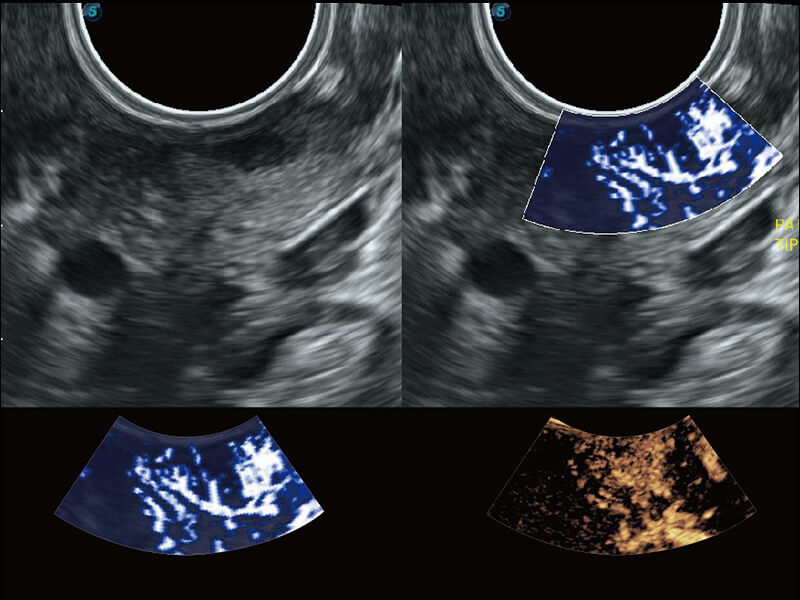

Micro F 显微血流成像 明察秋毫

高分辨率容积成像 栩栩如生

超宽频带技术,为容积成像带来优质的二维图像基础,为您呈现丰富的结构细节,栩栩如生地展示宝宝的宫内形态以及各种组织的立体结构。